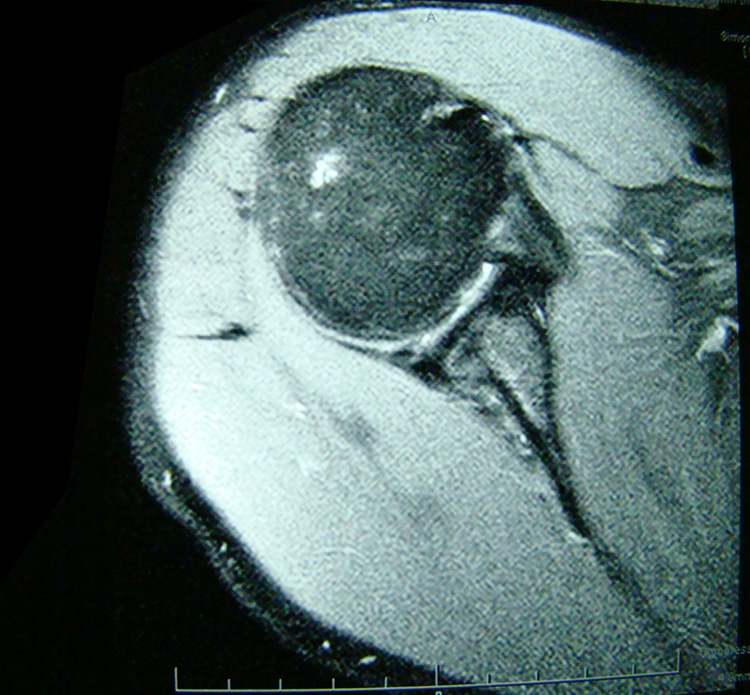

This patient presented with an ultrasound demonstrating a baseball-sized Baker's cyst behind the knee. The "after" film was taken 4 months after the 8th treatment of prolotherapy. He is now enjoying being pain and Baker’s cyst free. At three year follow-up, the cyst had not returned.[/toggle_content]

This patient presented with shoulder pain that interfered with work and exercise. The visible fluid-filled cysts on the “Before" MRIs are from chronically injured rotator cuff tendon roots.

The patient underwent treatments of a highly specialized fine-needling technique pioneered by Dr. Tallman.The follow-up MRI was done 2 months after his 6th treatment. He was released with a pain-free, full range of motion with unrestricted activities.